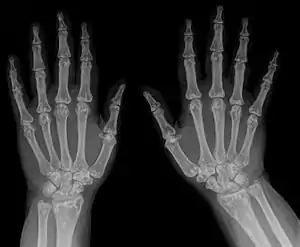

- Osteopoikilosis

- X-ray